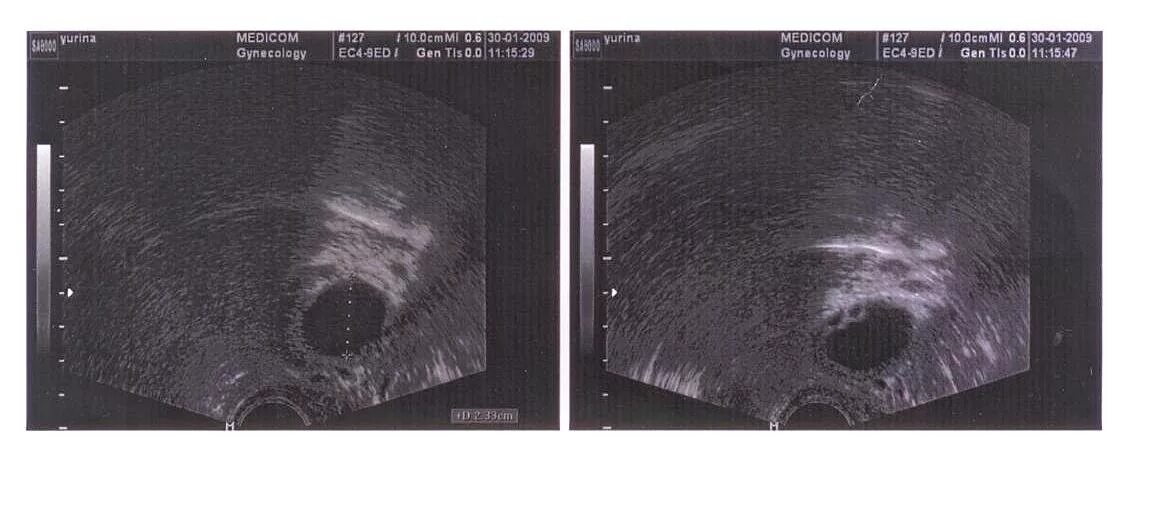

Узи яичников доминантный фолликул. доминантный фолликул на узи. фолликул доминантный фолликул. доминантный фолликул в яичнике.Фолликул яичника 20мм узи.. доминантный фолликул 17 мм на узи. фолликулометрия узи доминантный фолликул.Фолликулометрия узи доминантный фолликул. доминантный фолликул 16 ми. размер фолликула на 10 день цикла.Доминантный фолликул 17 мм на узи. доминантный фолликул узи 20 мм. фолликул яичника 20мм узи..Доминантный фолликул на узи. узи яичников доминантный фолликул. яйценосный бугорок на фолликуле. доминантный фолликул и желтое тело на узи.Доминантный фолликул в правом яичнике 18 мм. доминантный фолликул на узи.Фолликул яичника 20мм узи.. доминантный фолликул на узи.Узи яичников доминантный фолликул. доминантный фолликул на узи. доминантный фолликул узи 20 мм.Узи яичников доминантный фолликул. овариальный резерв яичников узи. фолликулометрия узи доминантный фолликул. узи фолликуломы яичников.Реазмер фалликулы перед овулацией. размер фолликула при овуляции.Фолликул 20Фолликулы в яичниках норма узи. узи фолликуломы яичников. ультразвуковые нормы фолликул яичника. узи яичников доминантный фолликул.Фолликул 20Овариальный фолликул в яичнике. строение фолликула яйцеклетки. строение фолликулов яичников.Примордиалтнвй фоллиекл сроение. типы фолликулов. строение первичнтот фолликула. яйцеклетка в фолликуле.Фолликулярный яичник на узи. узи яичников доминантный фолликул. персистирующий фолликул яичника узи. мультифолликулярные яичники на узи.Яйцеклетка в фолликуле. яичник с созревшим фолликулом. яичниковая фолликула в яичнике.Доминантный фолликул на узи. персистирующий фолликул на узи. узи яичников доминантный фолликул.Фолликул яичника 20мм узи.. узи яичников доминантный фолликул. доминантный фолликул на узи. доминантный фолликул после овуляции на узи.Фолликул яичника 20мм узи.. доминантный фолликул на узи. фолликул после овуляции на узи.Яйценосный бугорок на фолликуле на узи. преовуляторный фолликул на узи. доминантный фолликул на узи. фолликул 20 мм с яйценосным бугорком.Примордиальный фолликул. примордиальный фолликул яичника. однослойный фолликул. виды фолликулов яичника.Первичный яйцевой фолликул. первичный фолликул яичника. формирование фолликула в яичнике.Узи яичников доминантный фолликул. персистирующий фолликул на узи. доминантный фолликул на узи. фолликул яичника 20мм узи..Преантральный фолликул гистология. falikul. фолликулы расположены в.Преовуляторный фолликул на узи. доминантный фолликул анатомия. антральные фолликулы на узи.Фолликулы в яичниках норма. фолликулы в яичниках норма в 40 лет. фолликул доминантный фолликул.Доминантный фолликул на узи. фолликул яичника 20мм узи..Текальная оболочка яйцеклетки. на 3 день цикла доминантный фолликул 9 мм. строение доминантного фолликула. стадии созревания фолликула с размерами.Фолликулы. виды фолликулов. диаметр зрелого фолликула.Фолликул 20Овариальный фолликул. овулировавший фолликул на яичнике. фолликул яичника 20мм узи..Первичный фолликул. типы фолликулов. виды фолликулов яичника. стадии развития фолликула.Строение фолликула яичника анатомия. строение фолликула яичника. созревание фолликула в яичнике. строение яйцеклетки фолликулярные клетки.Строение первичного фолликула яичника. граафов пузырек анатомия. граафов пузырек яичника строение. строение граффового фалекул.Примордиальный фолликул. строение первичного фолликула. типы фолликулов. стадии развития фолликула.Первичный яйцевой фолликул. клетки гранулезы в фолликулах. строение фолликула гистология. примордиальный первичный вторичный и третичный фолликул.Персистирующий фолликул узи протокол. персистенция желтого тела яичника. персистирующие фолликулы яичников узи.Гранулезные клетки фолликула. фолликулярная фаза яичникового цикла. процессы происходящие в яичниках. циклические изменения в яичнике.Фолликулометрия норма по дням цикла. фолликулометрия протокол узи. узи яичников доминантный фолликул. фолликулометрия норма по узи.Схема развития фолликулов яичника. схема развития фолликулов яичника овуляция образование желтого тела. стадии развития фолликула схема. цикл созревания яйцеклетки.Фолликул морской свинки. строение фолликула раскраска. атретический фолликул. фолликул раскраска.Размеры фолликула по узи по дням цикла. желтое тело на 20 день цикла узи. размеры жёлтого тела по дням. жёлтое тело в яичнике на узи норма по дням цикла.Фолликул 20Нормальный яичник узи 7 день цикла. доминантный фолликул 19мм эндометрии 7мм узи. жёлтое тело на узи при беременности 7 недель. доминантный фолликул на 10 день цикла норма.Фолликул 20Функции фолликулов яичника. узи мониторинг созревания фолликула. фолликулы в яичниках 10 мм это норма.Узи яичников доминантный фолликул. яичники на узи норма. узи малого таза яичники. поликистоз яичников узи малого таза.Фазы созревания яйцеклетки схема. схема развития фолликулов яичника. фазы созревания яйцеклетки анатомия. этапы развития доминантного фолликула.Первичный фолликул вторичный фолликул. первичный вторичный третичный фолликул. примордиальны первичные фолликулы. вторичный фолликул яичника.Строение фолликула гистология. формирование фолликула в яичнике. созревание яйцеклетки анатомия. фолликул анатомия.Классификация фолликулов. число антральных фолликулов. классификация фолликулов яичника. размеры фолликулов в норме.Строение фолликула яичника гистология. граафов пузырек яичника строение. созревание фолликула гистология. фолликулы яичника гистология.Апоптоз фолликула яичника.Фолликулы. преантральные фолликулы. примордиальный фолликул яичника.Фолликулы в яичниках анатомия. строение фолликулы яйцеклетки анатомия. многослойный фолликул. стадии развития желтого тела.Первичный преантральный фолликул. преантральный фолликул гистология. примордиальный фолликул гистология. типы строения фолликула.Фолликул 20Доминантный фолликул узи 20 мм. узи яичников доминантный фолликул. геморрагическая киста желтого тела на узи. фолликул яичника 20мм узи..Фолликулы. яйцеклетка в фолликуле. фолликул это в биологии.Овариальный резерв яичников узи. овариальный резерв яичников норма. фолликулярный резерв яичников узи. доминантный фолликул 1.Четвертичный фолликул. строение третичного фолликула. многослойный фолликул. стадии развития фолликула в яичнике.Узи яичников 4 фолликула. фолликулы по периферии яичника что это. норма фолликулов. фолликул в яичнике на 5 день цикла.Узи киста правого яичника заключение. киста желтого тела узи заключение. эндометрий узи заключение. протокол узи фолликулярная киста.Цикл развития фолликула в яичнике. стадии развития желтого тела. схема развития овариального фолликула. строение фолликула гистология.Фолликулы. фолликул – структурно-функциональная единица. секреторный цикл фолликулярного тироцита. стенка фолликула представлена:.Строение фолликула гистология. вторичный фолликул гистология препарат строение. строение яичника гистология препарат. примордиальный фолликул гистология строение.Схема развития фолликула. этапы развития фолликула яичника. яйцеклетка в фолликуле. первичный фолликул.Оболочки фолликула. клетки фолликула. стадии развития фолликула. фолликул строение оболочки.Фолликулы в яичниках в 1 фазе цикла. гормоны фолликулярных клеток яичника. фолликулярный эпителий фолликула. фазы развития фолликула в яичнике.Этапы развития доминантного фолликула. типы фолликулов. строение доминантного фолликула. стадии развития фолликула.Яичники стадии созревания фолликулов. яичнике созревает доминантный фолликул. первичный фолликул яичника окружен. овариальный фолликул в яичнике.Овогенез яйцеклетки. схема развития фолликулов яичника. фолликулы в яичниках анатомия. строение фолликула яичника.Фолликулярные кисты яичников узи. фолликулярная киста яичника на узи. эндометриоидная киста на узи. фолликулярная киста левого яичника узи.Овариальный фолликул в яичнике. стадии развития желтого тела яичника. схема строения яичника в течении полового цикла. строение фолликула гистология.Строение яичника тека клетки. первичный и вторичный фолликул. стадии формирования желтого тела. стадии развития фолликула.Доминантный фолликул на узи. поликистоз яичников на узи. как выглядит овуляция на узи.